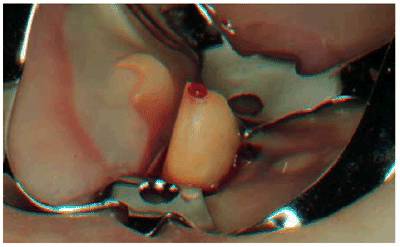

This is because if the pulp was accidentally exposed by a dental bur (Figure 19-34) or by traumatic injury, then only

the surface will show reversible inflammatory changes. If the pulp exposure is

under deep decay, then there is good likelihood that the inflammation has

affected a large portion of the pulpal tissue and even caused partial necrosis.

Figure 19-34: Pulp exposure during crown preparation. Pulp extirpation is indicated.